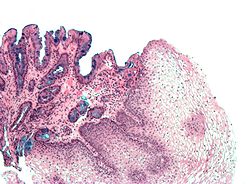

Barrettov jednjak označava prisutnost cilindričnog epitela u donjem dijelu jednjaka koji zamjenjuje normalni višeslojni pločasti epitel-tipičan je primjer za metaplaziju. Ovaj epitel koji nalikuje onome u želucu može bolje podnositi korozivno djelovanje želučane kiseline, međutim povećava opasnost od nastanka raka jednjaka.[7]

Imamo dva tipa metaplastičnih cilindričnih stanica: gastrične (želučane) koje su slične onima u želucu što se tehnički i ne smatra Barrettovim jednjakom i kolonične koje su nalik na epitel debelog crijeva. Obično se na biopsiji nađu oba tipa stanica. Metaplazija u kojoj stanice nalikuju onima iz debelog crijeva povezana je s genetski opterećenom populacijom.

Metaplazija je vidljiva na endoskopiji ali se uzorak mora pregledati mikroskopski da se utvrdi koji je tip stanica dominantan. Kolonička metaplazija je karakterizirana peharastim stanicama epitela i preduvjet je za postavljanje dijagnoze Barrettovog jednjaka.

Mikroskopska slika Barrettovog jednjaka. Alcian blue stain.